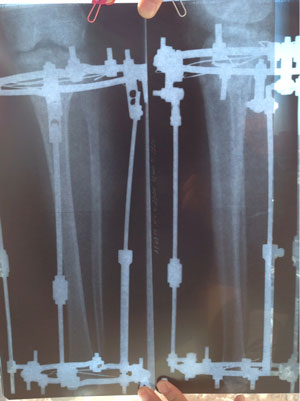

Рентген в 2 месяца.

Сращение идёт отлично, снятие аппаратов в 3 месяца!